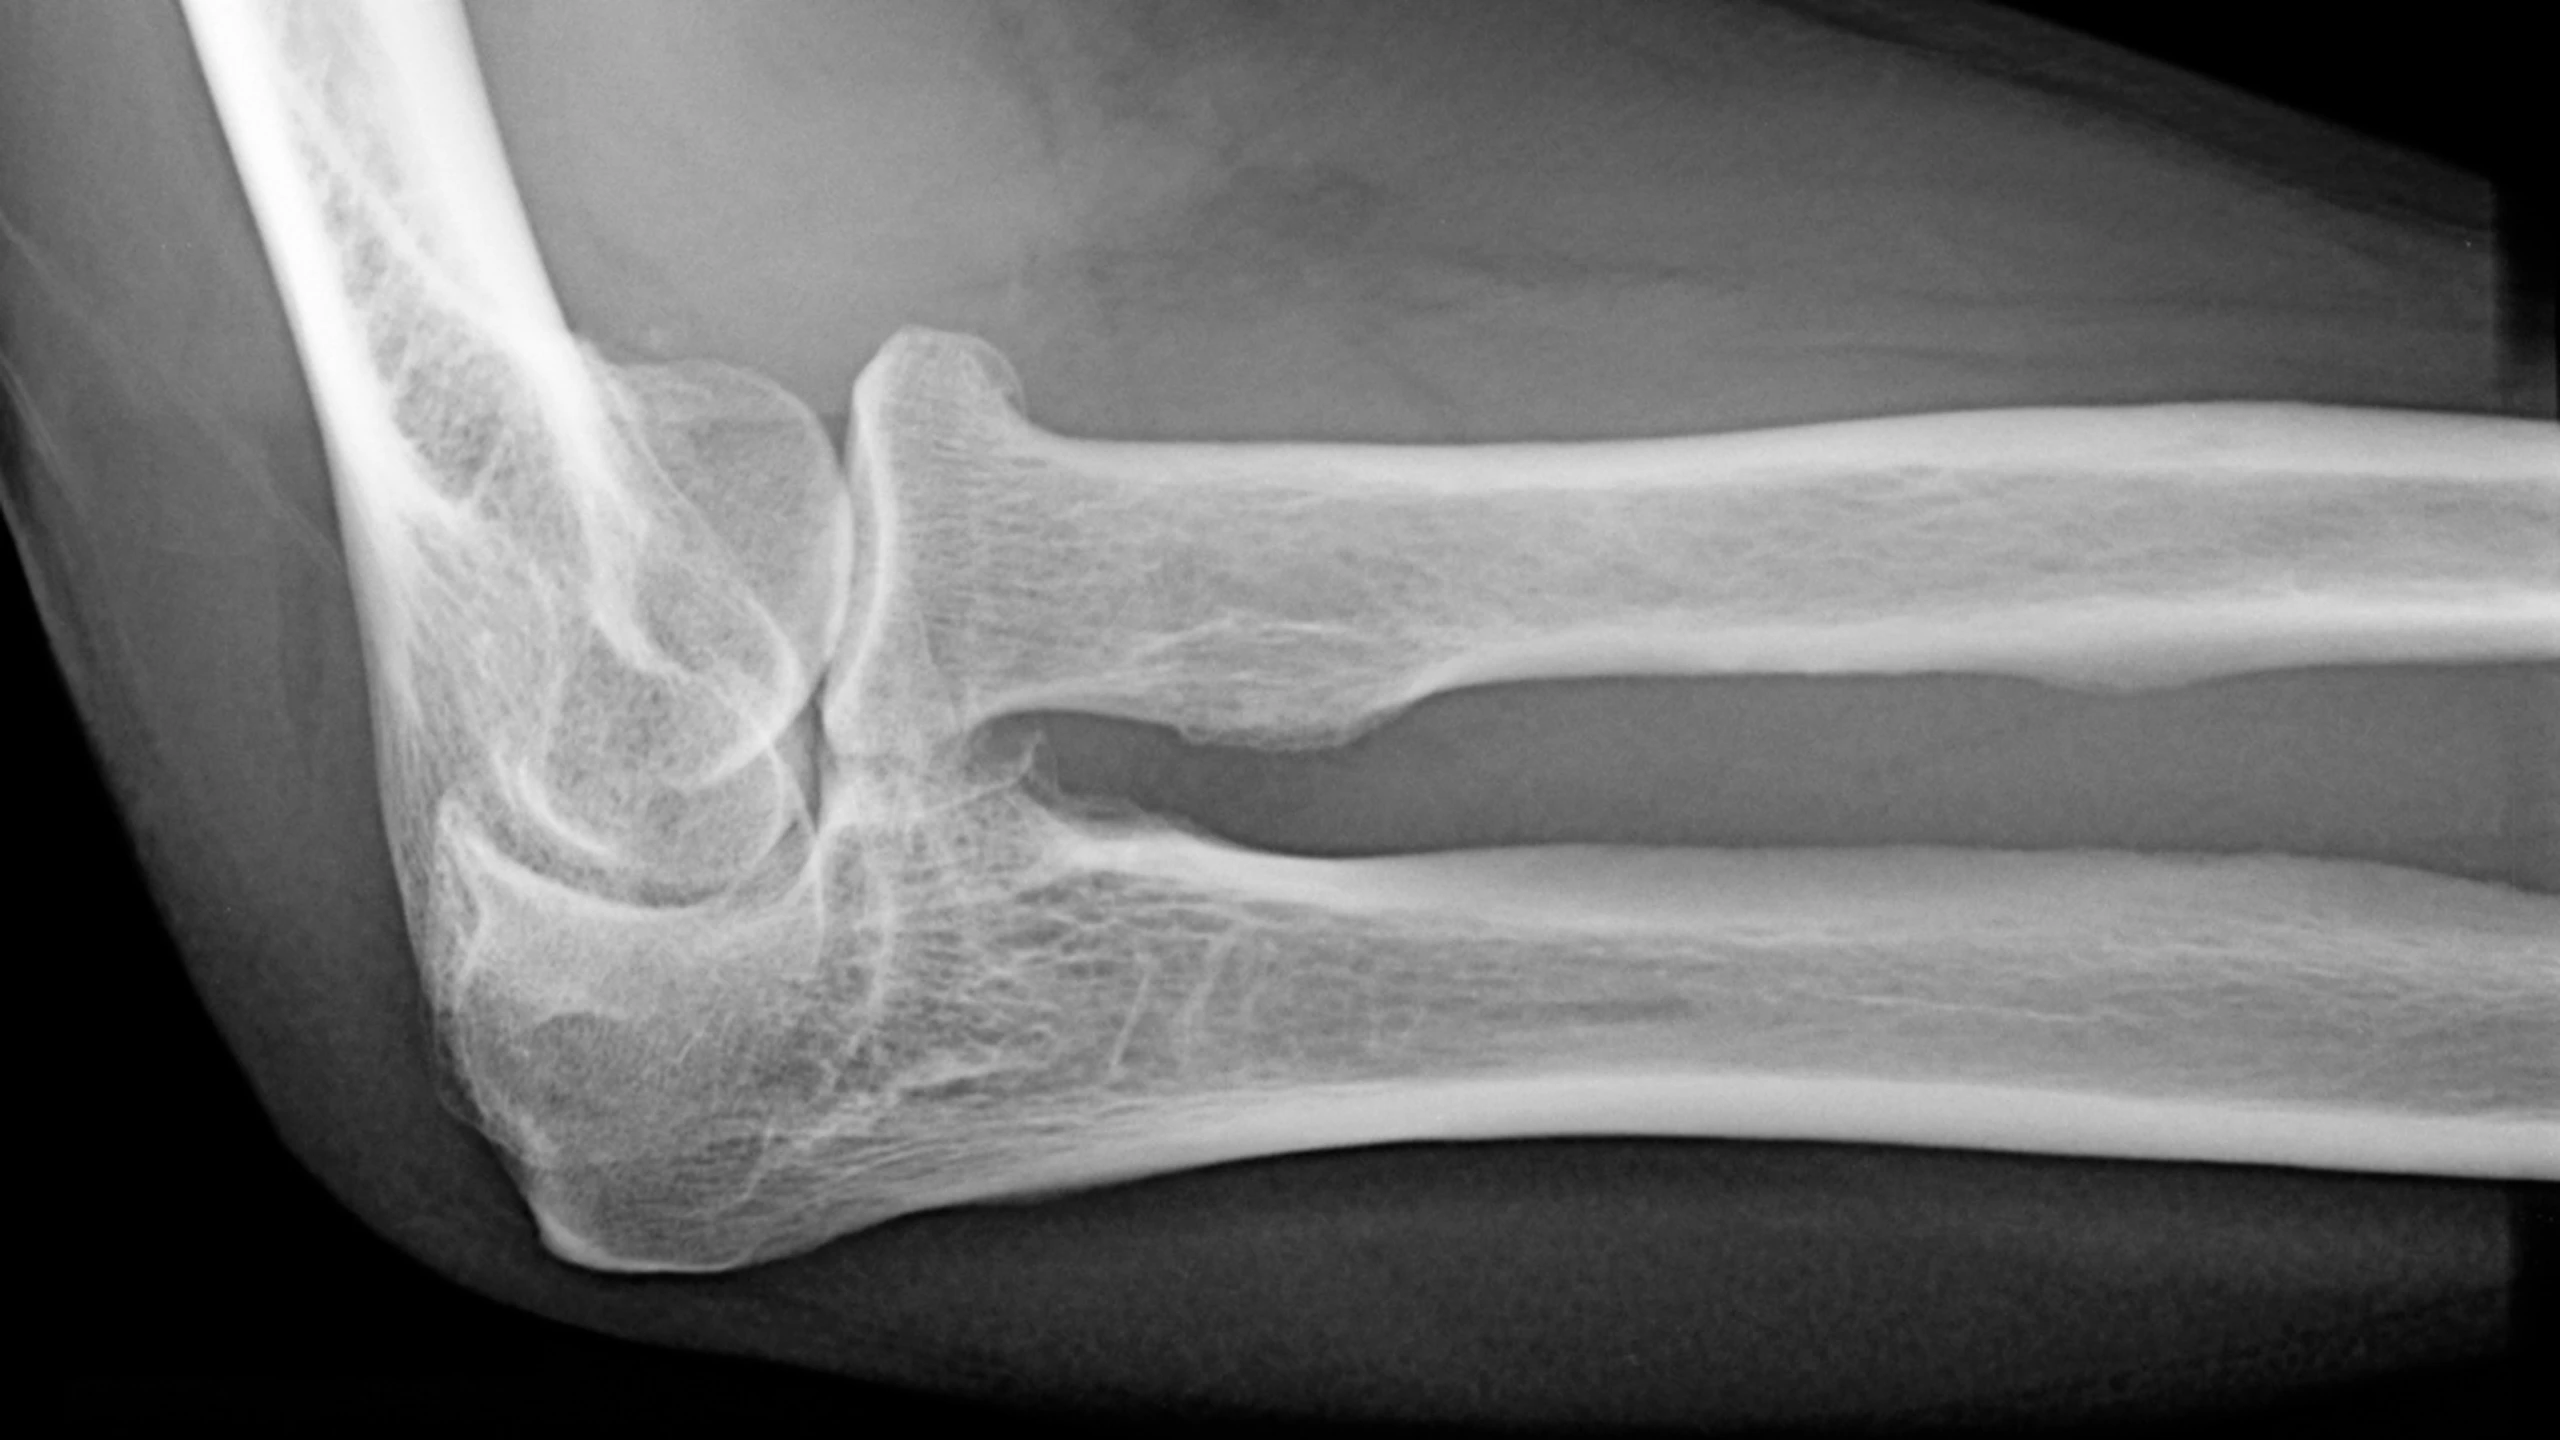

Khuỷu tay của bạn là một khớp được hình thành bởi ba xương kết hợp với nhau, bao gồm xương cánh tay, xương trụ và xương quay. Bao xung quanh khớp khuỷu có các thành phần như cơ, sụn, dây chằng, bao hoạt dịch giúp bảo vệ, cổ định và làm cho khớp khuỷu hoạt động trơn tru. Ngoài ra còn có thần kinh giữa và động mạch cánh tay chạy qua. Nhờ sự phối hợp của tất cả các thành phần trên mà khớp khuỷu có thể thực hiện được các động tác như gập, duỗi cẳng tay.

Đau khớp khuỷu tay khi có tổn thương bất kỳ thành phần nào của khớp bao gồm cơ, gân, dây chằng, bao hoạt dịch, xương, mạch máu hoặc dây thần kinh.

Khuỷu tay thường rất dễ bị trật khớp, đặc biệt ở trẻ em. Nếu đau khớp do tổn thương gân, cơ, dây chằng có thể là do một số môn thể thao và hoạt động sai tư thế trong cuộc sống hàng ngày. Viêm khớp dạng thấp, sau chấn thương cũng thường gây ra viêm và đau tại khớp khuỷu.